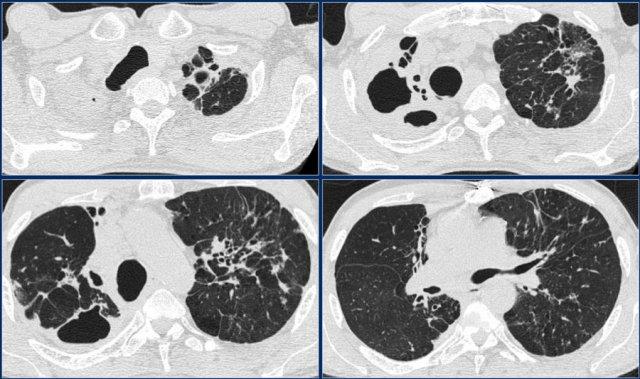

Bệnh nhân này nhập viện lần đầu với phim X quang ngực bên trái.

Hãy quan sát kỹ các hình ảnh trước.

Sau đó tiếp tục đọc.

Các dấu hiệu bao gồm:

- Các đám mờ bờ không rõ lan tỏa, có thể là các vùng đông đặc nhỏ.

- Hang ở thùy trên phổi phải.

Có thể nhận định đây là tái hoạt của lao tiềm ẩn.

Cấy đờm dương tính với vi khuẩn lao.

Phim X quang ngực chụp vài năm sau (bên phải) cho thấy:

- Xẹp thùy trên phổi phải

- Lệch khí quản

- Xơ hóa và tạo hang ở phần còn lại của thùy trên

- Xơ hóa tối thiểu và tạo hang ở thùy trên phổi trái.

Điều này được đánh giá rõ hơn trên CT.

Tiếp tục…

Cùng bệnh nhân

Lưu ý hình ảnh tạo hang, đặc biệt ở phổi phải.

Ở thùy trên phổi trái, có thể có giãn phế quản do co kéo (traction-bronchiectasis) liên quan đến xơ hóa.